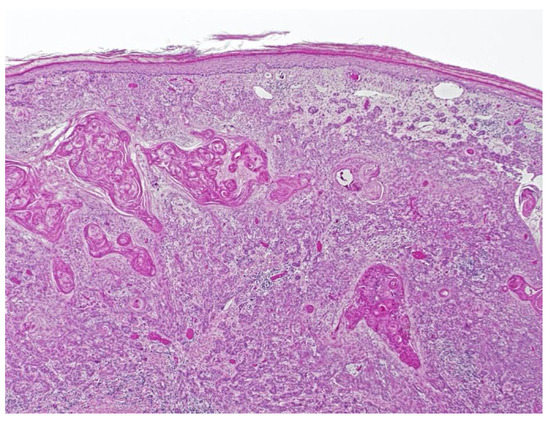

Figure 3.

Squamous cell carcinoma with acantholytic features.

Fourteen years after the transplant, the patient was seen in dermatology for a morbilliform drug eruption to clindamycin, which was treated with six weeks of oral prednisone. While being followed for her drug eruption, she developed a rapidly growing 3.5 cm fungating, ulcerated, and slightly tender nodule on her right dorsal hand. (Figure 2) Punch biopsy revealed a cutaneous squamous cell carcinoma with acantholytic features. (Figure 3) Immunohistochemical staining for P16 was negative. This test was performed to rule out co-infection with HPV.